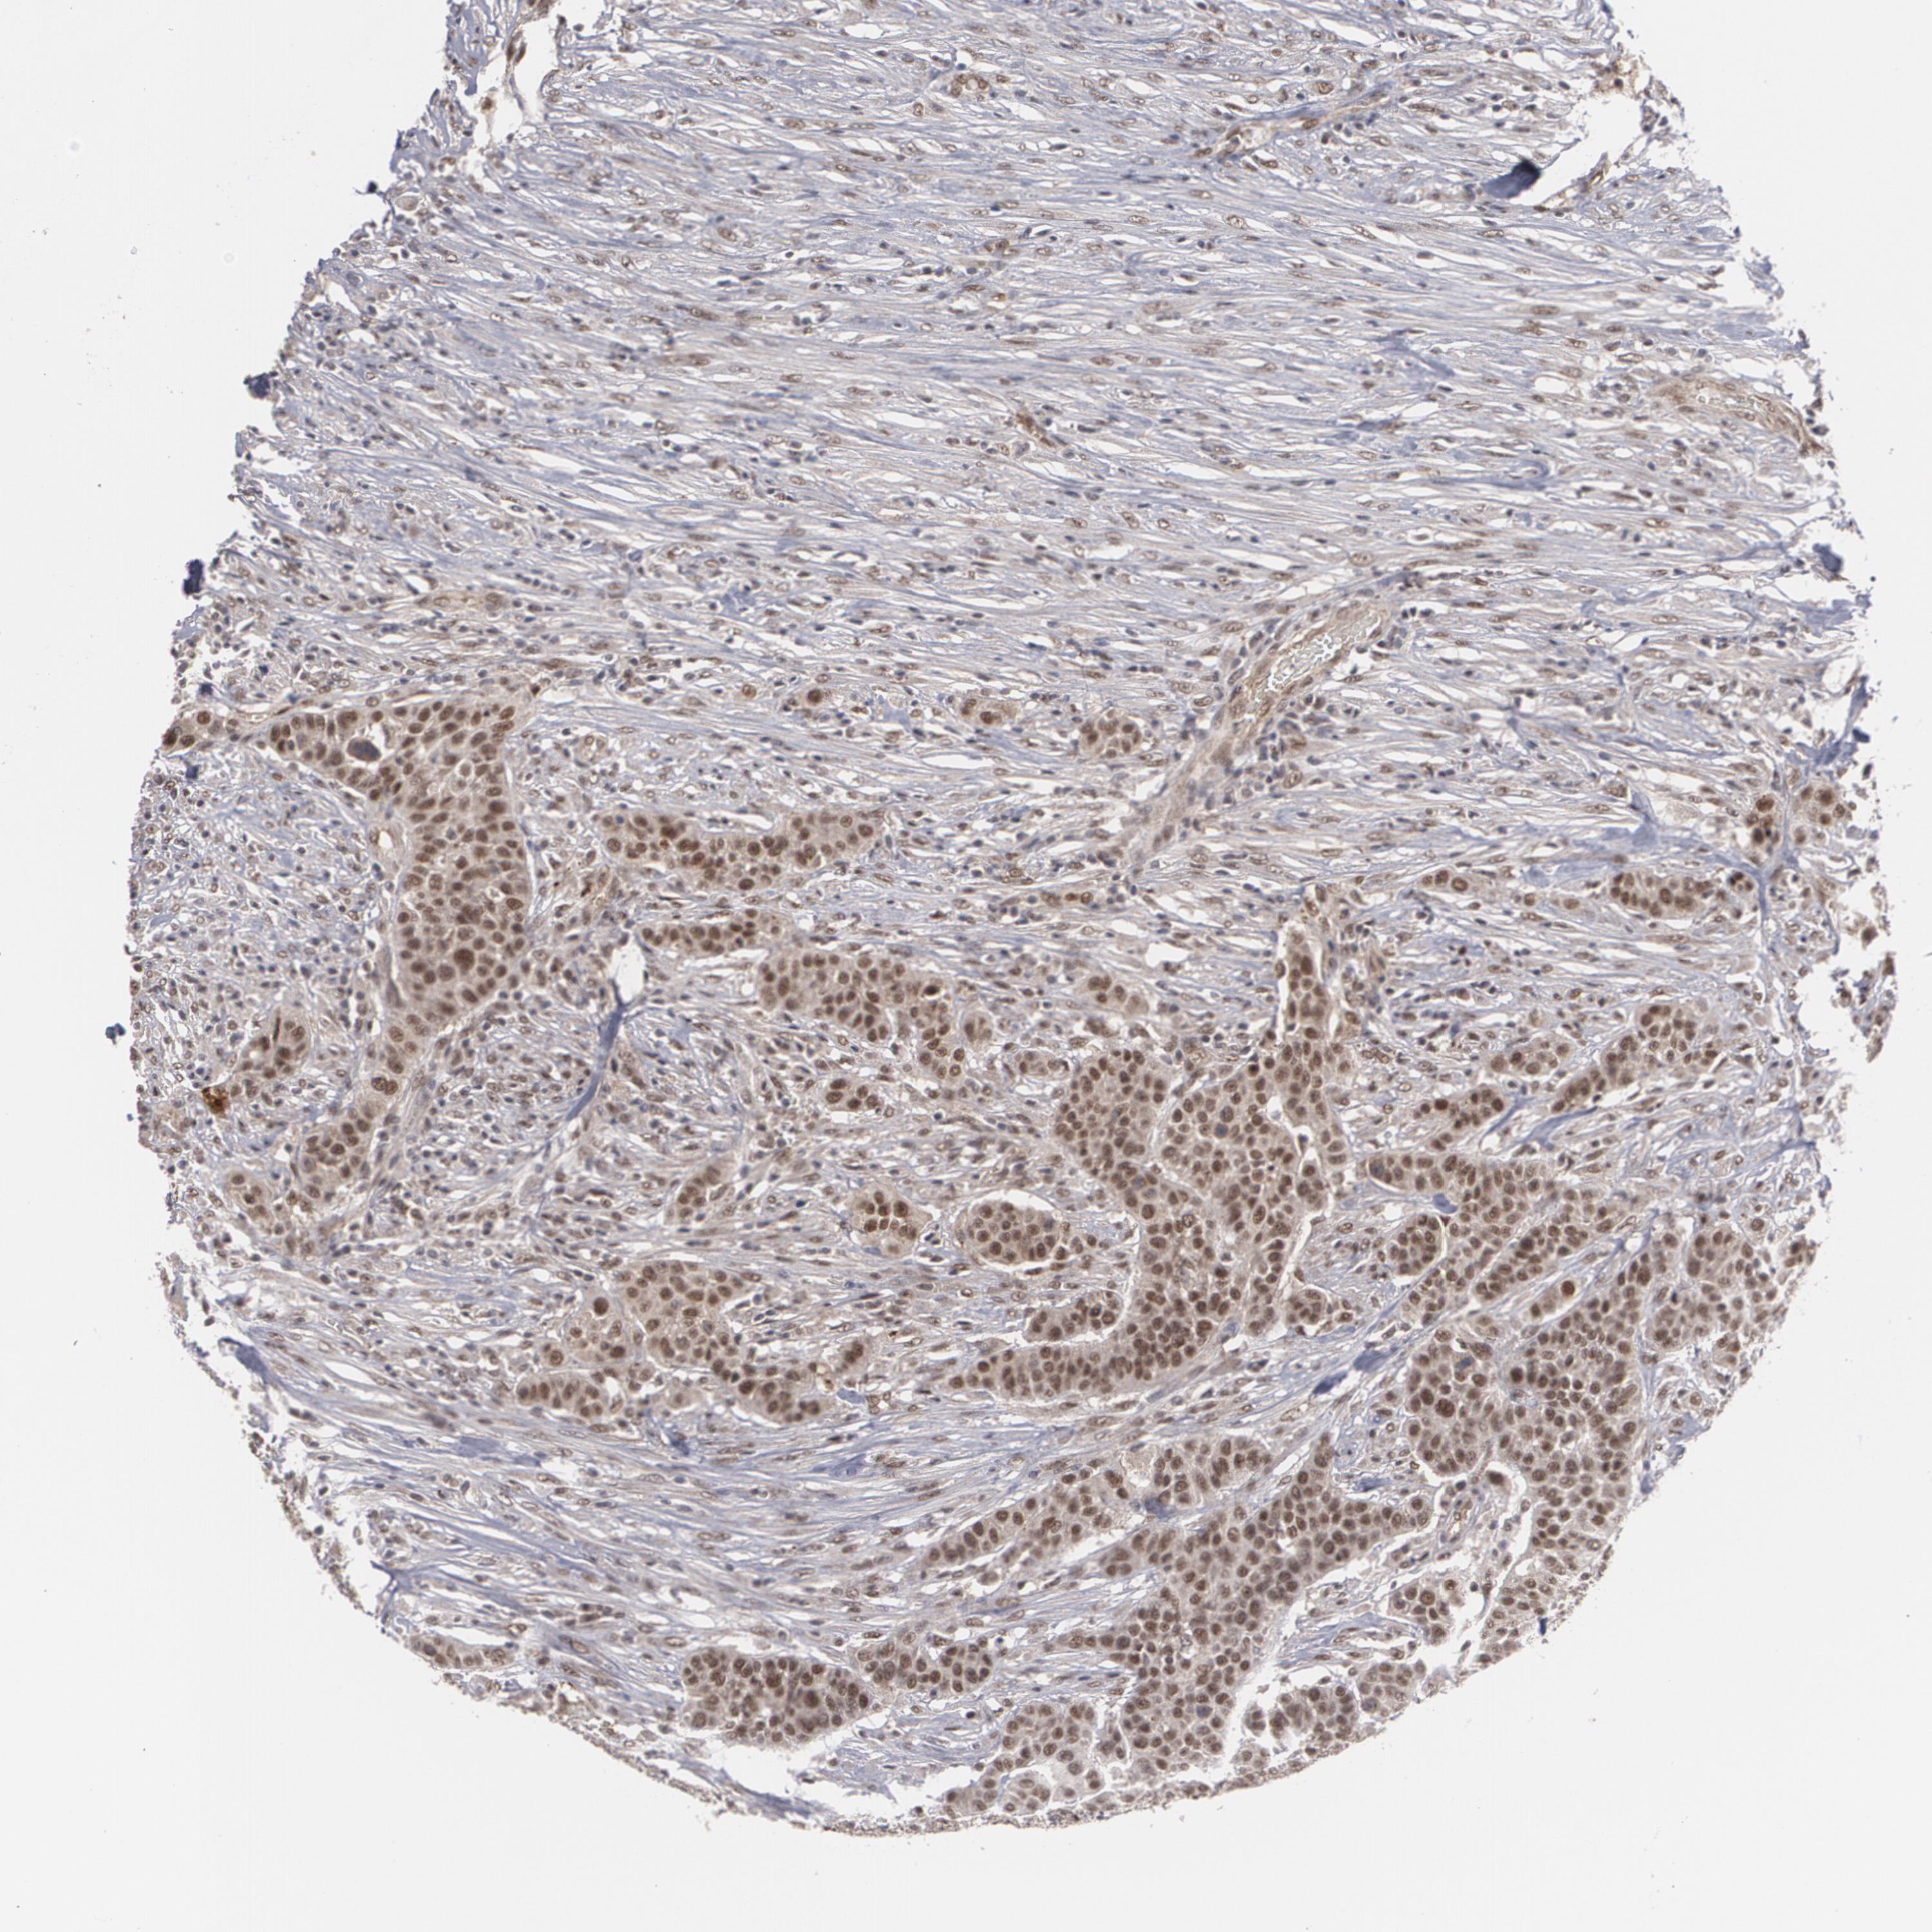

UROTHELIAL CANCER - Protein expressioni

A mouse-over function shows sample information and annotation data. Click on an image to view it in a full screen mode. Samples can be filtered based on level of antibody staining by selecting one or several of the following categories: high, medium, low and not detected. The assay and annotation is described here.

Note that samples used for immunohistochemistry by the Human Protein Atlas do not correspond to samples in the TCGA dataset.

Antibody stainingi

Antibody staining in the annotated cell types in the current human tissue is reported as not detected, low, medium, or high, based on conventional immunohistochemistry profiling in selected tissues. This score is based on the combination of the staining intensity and fraction of stained cells.

Each image is clickable and will lead to virtual microscopy that enables deeper exploration of all samples and also displays staining intensity scores, fraction scores and subcellular localization as well as patient and tissue information for each sample.

Antibody HPA001552

Antibody HPA001846

Staining

High

Medium

Low

Not detected

Intensity

Strong

Moderate

Weak

Negative

Quantity

>75%

75%-25%

<25%

None

Location

Nuclear

Cytoplasmic/membranous

Cytoplasmic/membranous,nuclear

Urothelial carcinoma, High grade

Urothelial carcinoma, Low grade

Adenocarcinoma, NOS